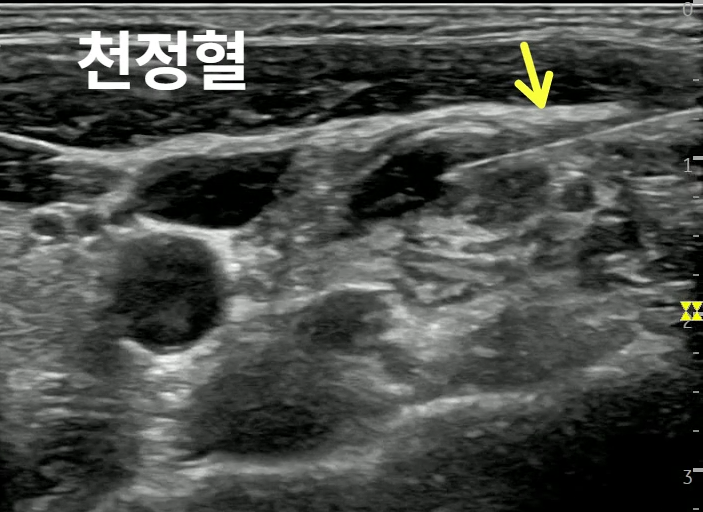

천정혈은 주변 구조물이 복잡하여

보다 정확한 시술**을 위하여

초음파 가이드로 약침을 시술했고요.

노란색 화살표로 표시한 특수침이

천정혈로 들어가는게 보이시죠?